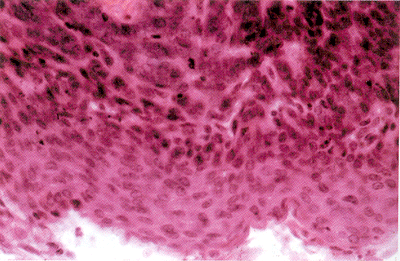

眼科图谱睑基底细胞癌1

睑基底细胞癌